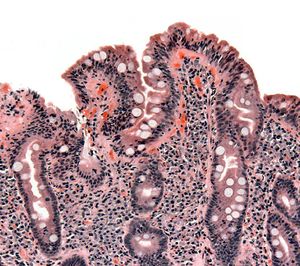

خزعة من الأمعاء الدقيقة تبين الداء البطني ظاهراً بتقصف الخملات، crypt hyperplasia, والخلايات الليمفية تتغلغل في crypts | |

التنظير العلوي للجهاز الهضمي مع أخذ الخزعات النسيجية هو حجر الأساس في تشخيص داء بطني، يجب الوصول إلى المعي الاثني عشري و المعي الصائم حتى يكون التنظير مجدياً، كثير من الخزعات المأخوذة من مرضى داء بطني قد تبدو سليمة و لذا يجب أخذ عدة عينات نسيجية من مناطق مختلفة حتى يكون التنظير دقيقاً ومثمراً.

تعتبر الخزعة الأكثر دقة في تشخيص الداء الزلاقي. يمكن الحصول على هذه الخزعة بالتنظير المريئي المعدي الإثناعشري. أثناء هذا الإجراء، يقوم الطبيب بإدخال منظار داخلي طويل مرن عبر الفم حتى الوصول إلى الإثناعشر. يمكن بعدها إمرار أداة خزع عبر قناة في المنظار لأخذ العينات من البطانة المعوية. يتم عادة أخذ عينات عديدة لزيادة دقة التشخيص. يمكن بعدها دراسة الخزعة تحت المجهر للبحث عن فقدان الزغيبات وغيرها من خصائص الداء الزلاقي مثل زيادة عدد اللمفاويات.